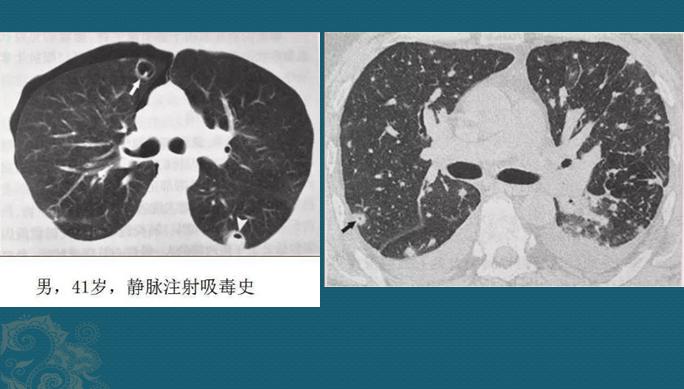

血源性的通常比较重!金葡菌一旦得势,形成局部脓肿大量繁殖,细菌入血,就像野草种子一样,随血液可以到达全身任何部位,常见的有骨髓、关节、大脑、双肺、肾脏等。

如果它们抵达肺部小血管周围生根发芽,就会制造各种毒素引发炎症,表现为多发点片状影或类圆形结节影,边缘清晰或模糊,沿支气管血管束或肺外周和基底部分布,因为是化脓性感染,多数结节最后会坏死、液化,形成空洞,当损伤血管或者形成血管内菌栓堵塞还可以引起远侧肺组织缺血坏死(肺梗死),形成胸膜下楔形肺实变影。

这些都是金葡菌小草刚发芽,多发小结节、小斑片影,有的形成了小空洞和小气囊,部分与血管关系密切,提示病菌是从血道来源引起肺部播散,及时抗生素治疗可以压制炎症发展。